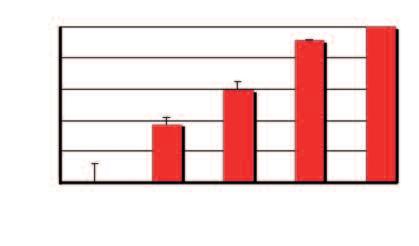

Aumento del numero dei decessi dovuti al cancro nei diversi gruppi di età, dal 1970 al 2000

Età dei pazienti 70 - 79 anni

Età dei pazienti 60 - 69 anni

Età dei pazienti 50 - 59 anni

Dati statistici per gli USA, dati comparabili per l’Europa. Fonte: Journal of the American Medical Association, 2005